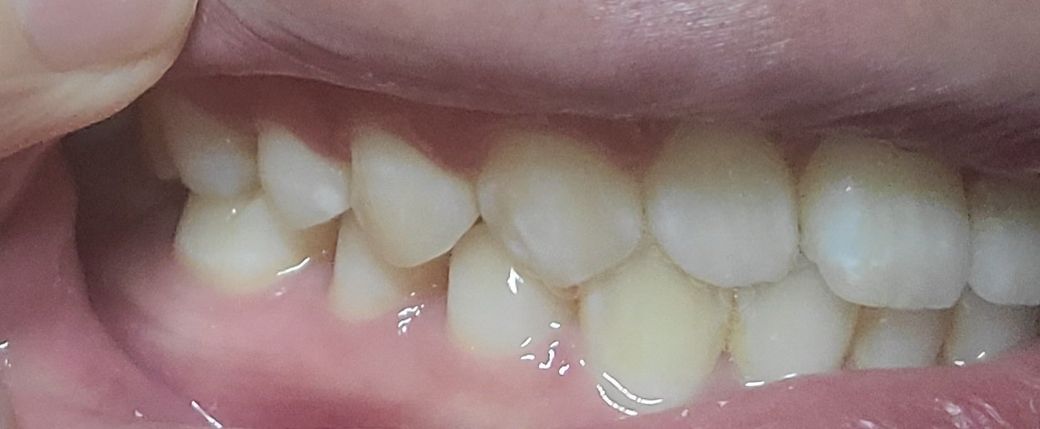

#작은 어금니쪽이 반대쪽과 다르게 딱맞는느낌이 아니고 공간이 남은느낌이들어요 그냥 제기분탓인지 모르겠네요.

왼쪽이 제1소구치쪽부터 교합이 아주 이상적인 교합은 아닙니다. 또한, 오른쪽 2번째 치아는 원래 위 치아가 아래치아를 덮어야하는데, 그렇지 않고 치아끼리 바로 닿습니다. 이 경우 치아에 무리가 갈 수 있습니다.

왼쪽 소구치와 대구치는 사진으로만 보기에는 정상적으로 교합하고 있는것으로 보입니다.